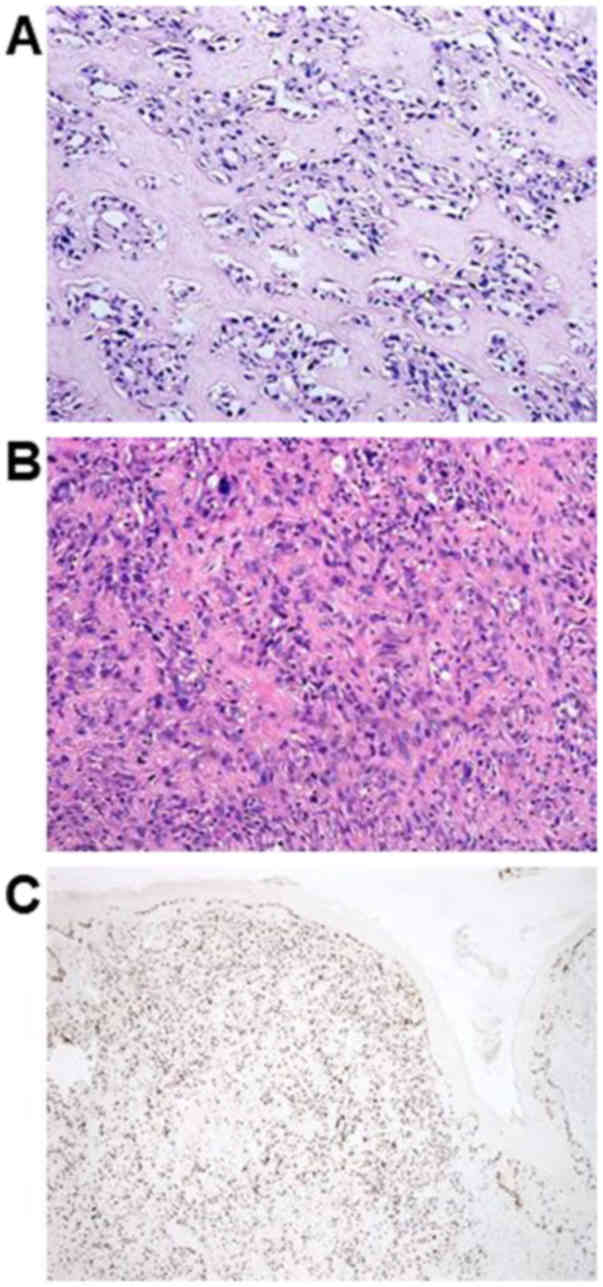

as a spindle cell sarcoma highly suggestive of OS. For details, the

histological findings of the initially diagnosed specimens revealed

an irregular arrangement of spindle- or oval-shaped tumor cells,

accompanying eosinophilic matrix suggesting osteoid formation. Most

of the lesions showed mild atypia with rich osteoid formation

(Fig. 1A). Conversely, tumor cells

showing high-grade atypia with low osteoid formation existed in

part (Fig. 1B). According to

immunohistochemical examination, Ki-67 labeling index was 30–40%

(Fig. 1C). Tumor cells were

positively stained for CD56 and were partially positive for smooth

muscle actin. The cells were negatively stained for CD34, S100, or

bc1-2.

atypia showed in Fig. 1A-C, it was